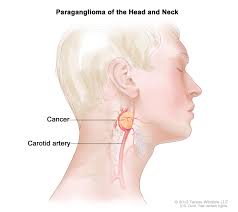

Pancreatic adenocarcinoma (PAAD) Pheochromocytoma and Paraganglioma (PCPG)

Pheochromocytoma and Paraganglioma (PCPG) Prostate adenocarcinoma (PRAD)